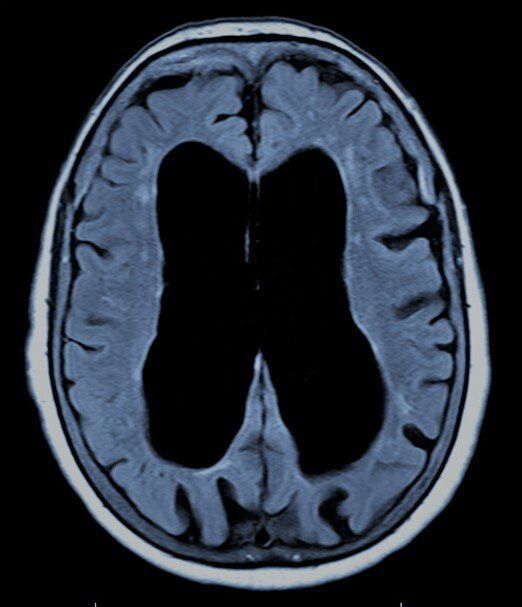

HIDROCEFALIA

La hidrocefalia es una condición médica en la que hay una acumulación excesiva de líquido cefalorraquídeo (LCR) en el cerebro.

Este líquido, que normalmente protege y amortigua el cerebro, puede ejercer una presión dañina cuando se acumula en exceso.

La hidrocefalia puede afectar a personas de todas las edades, pero es especialmente común en bebés y personas mayores